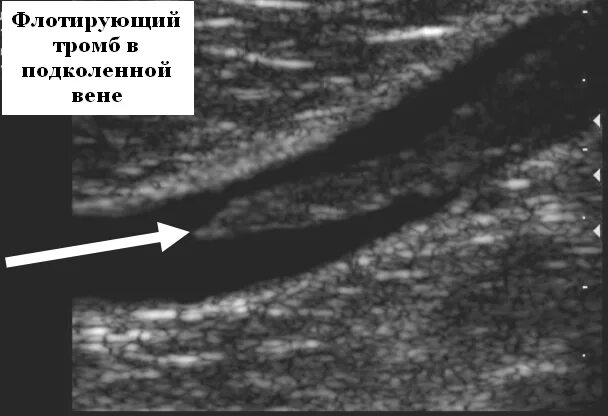

Как проверить сосуды на наличие тромбов